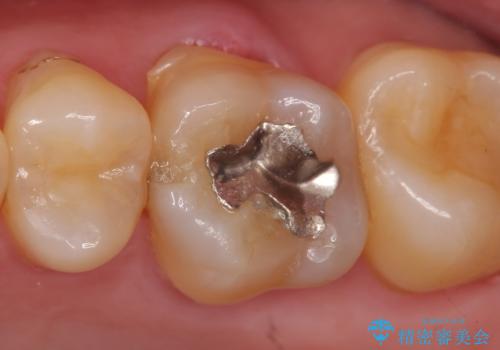

セラミックインレー 虫歯で欠けた歯の治療